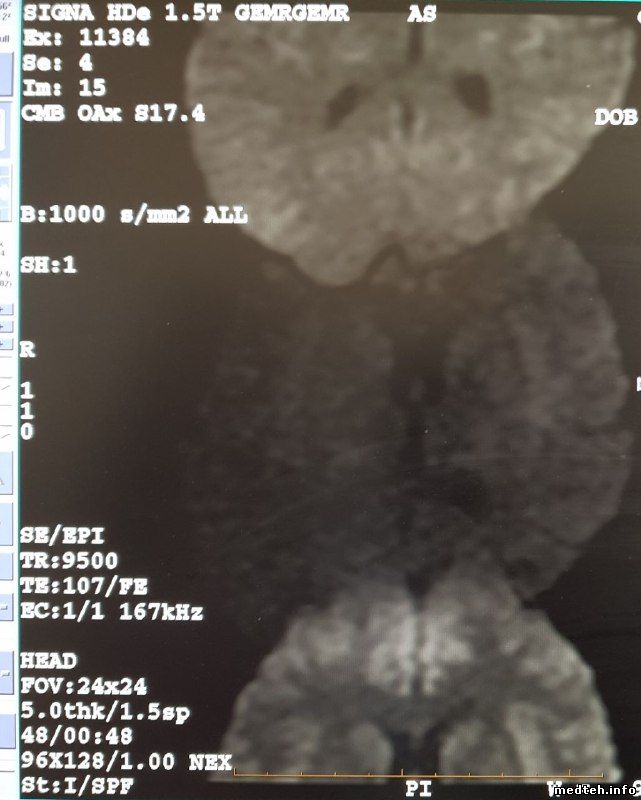

| Форум медтехников Медицинское оборудование (тех. разделы) Компьютерные и магниторезонансные томографы Signa HDe 1.5T (Проблемы с аппаратом) |

| Signa HDe 1.5T | |||||||||